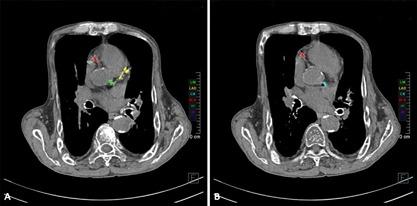

Secondary hyperparathyroidism (SHPT) is a long-term complication of chronic kidney disease-mineral and bone disorder (CKD-MBD). SHPT is characterized by hyperplasia of the parathyroid glands and abnormal secretion of parathyroid hormones (PTH), calcium and phosphorous metabolic disorders, renal osteodystrophy, vascular and soft tissue calcification, malnutrition, and other multiple system complications, which can seriously affect the quality of life of the patient and increase the risk of cardiovascular disease and mortality rate. Uremic leontiasis ossea (ULO) is a medical condition only rarely encountered clinically. SHPT causes craniofacial bone deformity accompanied by lesions of the nerve, cardiovascular, respiratory, bone, or other systems within the body. The case discussed here is related to severe SHPT. A 62-year-old male patient was suffering from leontiasis ossea, pectus excavatum, vascular calcification, spontaneous bone fractures, and lower limb deformities. He was undergoing hemodialysis and given total parathyroidectomy (TPTX) with autotransplantation (AT). We further analyzed the multivariate therapeutic effects of TPTX on this patient in order to provide clinical data for standardized treatment of individuals with CKD-MBD.

继发性甲状旁腺功能亢进(SHPT)是慢性肾脏病 - 矿物质和骨异常(CKD - MBD)的一种长期并发症。SHPT的特征是甲状旁腺增生以及甲状旁腺激素(PTH)分泌异常、钙和磷代谢紊乱、肾性骨营养不良、血管和软组织钙化、营养不良以及其他多系统并发症,这些会严重影响患者的生活质量,并增加心血管疾病风险和死亡率。尿毒症性骨性狮面(ULO)是一种临床上很少遇到的病症。SHPT会导致颅面骨畸形,并伴有体内神经、心血管、呼吸、骨骼或其他系统的病变。这里讨论的病例与严重的SHPT有关。一名62岁男性患者患有骨性狮面、漏斗胸、血管钙化、自发性骨折和下肢畸形。他正在接受血液透析,并接受了甲状旁腺全切术(TPTX)及自体移植(AT)。我们进一步分析了TPTX对该患者的多变量治疗效果,以便为CKD - MBD患者的标准化治疗提供临床数据。